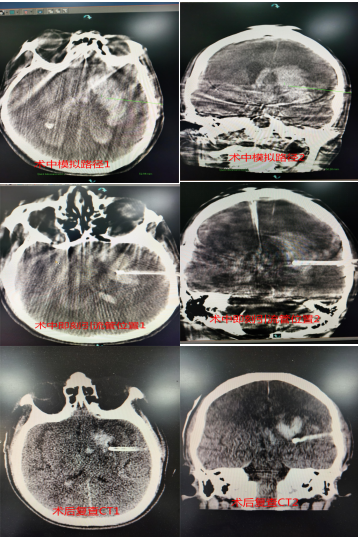

患者为64岁男性,以“突发意识障碍6小时”主诉入院,颅脑CT平扫示左侧基底节区脑出血,量约50ml,患者意识不清,颅内出血量大且中线偏移明显,手术指征明确,为及时高效地给予患者治疗,李帅和科室医生经过与家属反复沟通协商,最终决定行“DSA引导下颅内血肿钻孔引流术”。术中患者仰卧位行DynaCT并标记和模拟穿刺路径、方向及深度,经皮锥颅后,按预先模拟路径将引流管穿刺至血肿中心部位,再次行DynaCT明确引流管位置,缓慢抽吸出约20ml暗红色血肿,留置引流管于血肿腔并固定,术后持续引流5天后复查示大部分血肿消失,给予拔出引流管,患者恢复顺利。